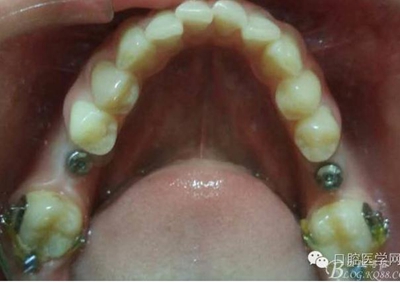

拔除18 28 38 48 后 47 遠(yuǎn)中植入支抗釘

因?yàn)榛颊咭蟀朐聝?nèi)完成,所以同期植入韓國(guó)豋騰4.5*10mm種植體